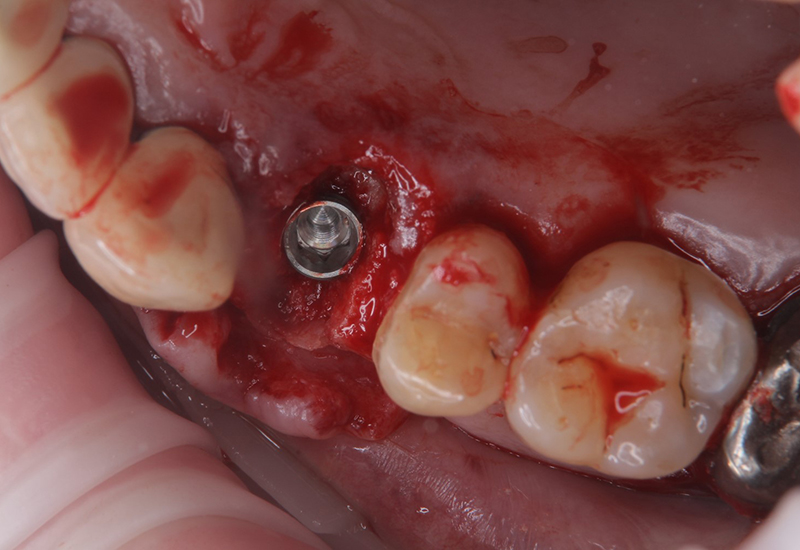

治療中の写真

サージカルガイド

左上5にインプラント埋入の為のドリル用ホールあり